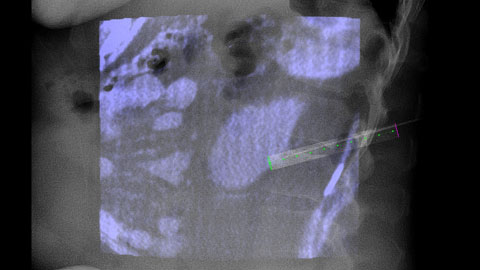

XperGuide Ablation provides comprehensive assistance for treatment planning and live needle guidance. It offers unique Parallax Correction to plan needle trajectories for off-center lesions [9].

XperGuide provides highly accurate live image guidance of each needle to a targeted position by overlaying pre-planned trajectories with fluoroscopic imaging [10].